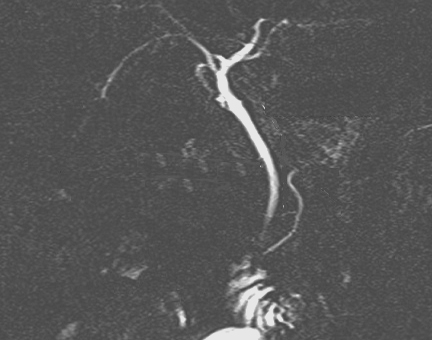

Image radiologique cholangio-wirsungo-IRM normal des

canaux pancreatiques ,de la vesicule biliaire et des

voies biliaires principale |